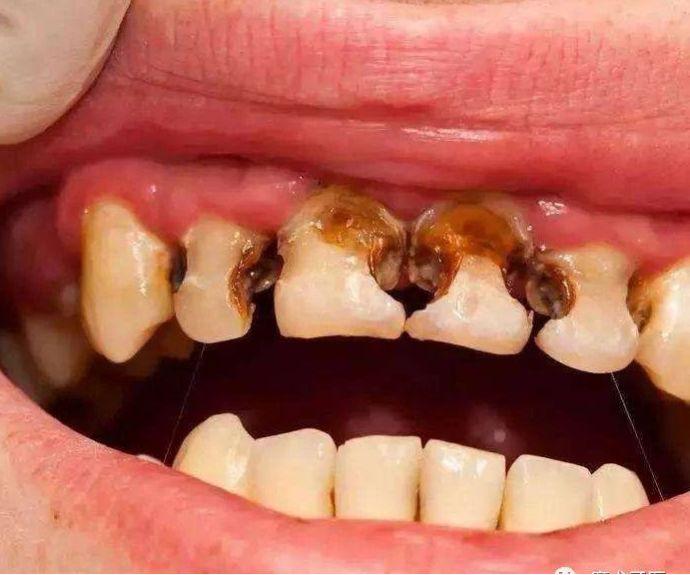

新的一年,新的變化。家長們,你們有沒有發(fā)現(xiàn)自己的孩子也有了新的變化:個(gè)子長高了,性格更加不羈了,牙齒也爛得差不多了(齲齒)。

中國兒童的齲齒狀況總體令人擔(dān)憂,哪怕不是留守兒童,如果身邊的父母疏于孩子的口腔健康教育,放任其養(yǎng)成愛吃糖常喝可樂刷牙不自覺等等壞習(xí)慣,終牙齒的境況也基本上類似。

而且有這樣的一種現(xiàn)實(shí),哪怕全口牙齲壞也鮮有家長為此主動(dòng)去看牙醫(yī),更多的是當(dāng)孩子出現(xiàn)了劇烈牙痛或者牙齦上長出了令家長們驚恐的如圖示腫物(恐癌心理)才被迫就診,這是一種中國式特色——反正乳牙都是要換掉的,單純齲齒治不治無所謂。

齲齒,俗稱蛀牙,蟲牙,但與蟲子完全搭不上邊,一定要搭的話,那蟲子就是細(xì)菌——變形鏈球菌為主。它作為一種產(chǎn)酸菌,只有在含糖和碳水化合物豐富的基質(zhì)上進(jìn)行化合作用才會(huì)酸蝕牙齒,而甜食,牛奶,碳酸飲料等等為它提供了充足條件。牙齒從酸蝕到脫礦崩解需要一定的時(shí)間,上面所見的嚴(yán)重齲齒病例,本來有相當(dāng)長的時(shí)間去進(jìn)行早期干預(yù),無論是醫(yī)學(xué)干預(yù)還是行為改變,都能不同程度地影響疾病進(jìn)展,不致形成“豁耙齒”的境地。